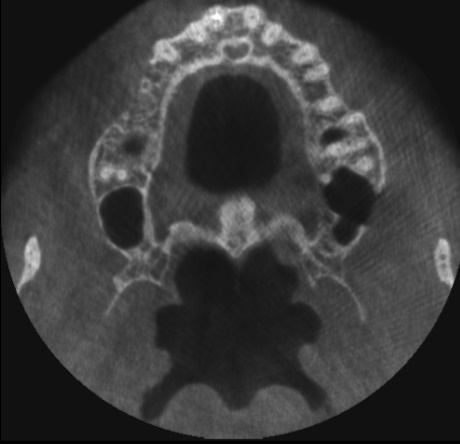

Пропила 2 курса антибиотиков. Хирург сказал, что все зубы в порядке, и отправил домой нервы лечить. Рентгенолог увидела повреждения и сказала не есть больной стороной и вообще не жевать. Это избавило меня от постоянной боли. Но стоит только дотронуться до семёрки, появляется неприятное очущение, как будто он висит на волоске. И в месте удалённой 5 зуд. Как будто кость сломана. Фото с 3д рентгена во время курса антибиотиков.

Прикрепленые фото

По этому снимку можно сказать, что немного повреждена передняя стенка, но это не является проблемой. К хирургу обратиться стоит, для того чтобы оценить процесс заживления.